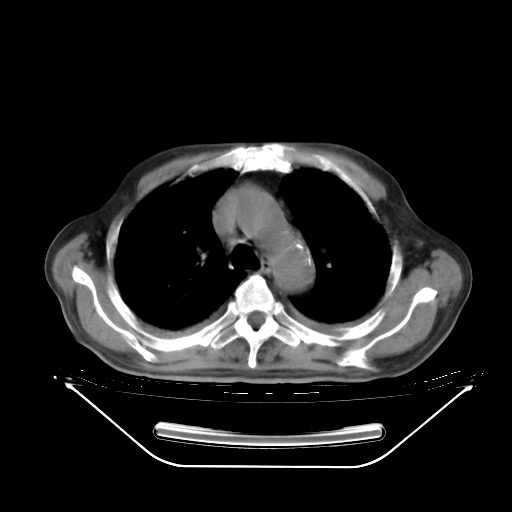

胸腹部CT,诊断意见:左上肺叶钙化灶、左侧胸膜局限性增厚并钙化、胆囊炎。描述部分肺组织呈磨玻璃样改变。

今天复查肺部CT,发现双肺广泛磨玻璃样改变。所以我把3月19日和5月9日相隔50天的肺部CT上传。请大家会诊。

2009年3月19日肺部CT片。

2009年3月19日肺部CT

大致读了系列胸部CT:纵隔窗无明显异常,肺窗:从4、27至今:主要是双肺中下野外带可见毛玻璃样改变,目前处于急性肺泡炎阶段,至于原因考虑1、结替组织或胶原血管性疾病所致?2、恶性疾病如恶组在肺部所致的表现或细支气管肺泡癌?3、药物或其它原因如肺蛋白沉着症所致肺泡炎目前不太可能?总之,明天就去请我院的呼吸科、感染科、血液科和临免专家会诊哈。